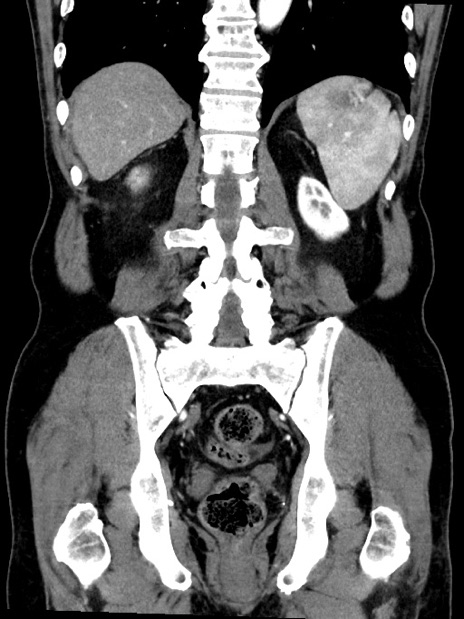

症例35(冠状断像)

【症例】70歳代 男性

【主訴】腹部膨満、嘔吐

【現病歴】昨日より腹部膨満感出現。本日増悪し、仙痛出現。嘔吐あり、受診。

【既往歴】糖尿病、胆摘後

【身体所見】BP 149/80mmHg、HR 74/min、BT 35.9℃、腹部:膨満、軟、圧痛なし。腸雑音減弱あり。上腹部正中切開瘢痕あり。

【データ】WBC 13500、CRP 1.72